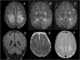

Thiamine deficiency neuropathy

Thiamine deficiency is a medical condition of low levels of thiamine (vitamin B1). A severe and chronic form is known as beriberi. [Source: Wikipedia ]